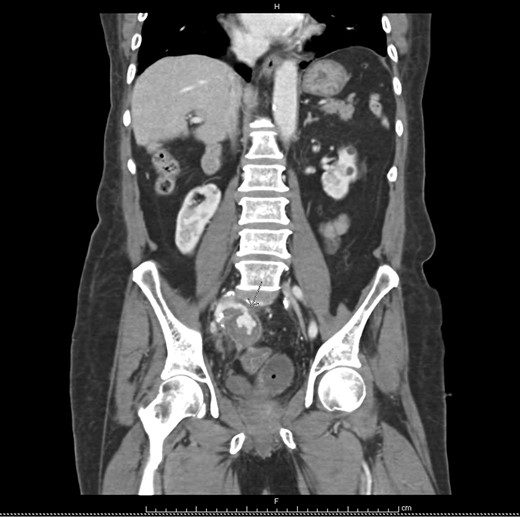

At Emergency department, physical exam showed hypotension blood pressure 70/50 mmHg and per rectal exam showed blood clot with enlarged prostate. After resuscitation until stable vital sign, he was sent for colonoscopy but cannot be evaluated due to a lot of blood clots in the rectum. He was admitted for observation and we planned to repeat colonoscopy again following day because he was stable and bleeding was stopped. Following day after admitting, he had massive lower gastrointestinal bleeding again fresh blood ~1000 ml from his anus. His blood pressure was lower 80/50 mmHg. After stabilization, we planned to send the patient to angiogram for embolization. But the patient had a problem vascular access site and then send to computed tomography angiography (CTA) for evaluate access site. We found 3 cm aneurysm of right internal iliac artery with partial thrombus and attached to rectosigmoid colon with leakage of contrast into sigmoid lumen (Figs 1–2). He was sent to operating room during transferring we gave blood transfusion and then emergency explore laparotomy was performed, the operation performed by partial aneurysmectomy, ligated right internal iliac, wedge resection rectum wall and temporary abdominal closure with swab packing due to bowel distension and abdominal pressure was high. The operative time was around 3 hours and blood loss 6000 cc. He was sent to operating room for change swab packing on Day 3 and permanent abdominal closure on Day 5. During postoperative period, he developed acute cholecystitis and underwent open cholecystectomy. After admit for 1 month, he was discharged with fully recovery.

Axial view iliac aneurysm with partially thrombose contact rectosigmoid colon and contrast leak.